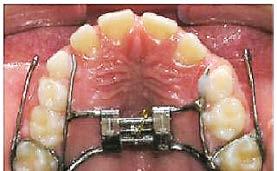

2. Con base en el tratamiento indicado, realizar la colocación oportuna

de las aparatologías adecuadas para preservar o en su caso, recuperar el espacio, considerando la edad del paciente y la complejidad del caso a tratar37,38 (Figura 25).

Etapa ortopédica

Tiene como objetivo, la corrección de las disarmonías maxilomandibulares en su dimensión, proporción e interrelación durante la oclusión; en la que la colocación de aparatos dependerá de los planos craneofaciales a corregir (transversales o sagitales), para estimular su crecimiento o redirección de los mismos; lo que a la vez, influirá directamente a la estimulación de la osteogénesis a nivel de las suturas óseas no consolidadas y en las áreas cartilaginosas ya sea en macizos óseos de desarrollo intramembranoso o endocondral, logrando generar espacio suficiente para el trayecto y erupción canina.24

En el colapso maxilar, por ejemplo, el primer paso es corregir el plano transversal. No podremos generar el espacio necesario para el acomodo del canino y posiblemente de los dientes adyacentes en el hueso alveolar, si no existe la zona ósea basal específica que lo soporte. Los diferentes tipos de aparatos usados para este objetivo dependerán de la edad del paciente o el grado de colapso y/o profundidad de la bóveda palatina, ya que el diseño de estos estará sujeto a las condiciones anatómicas y clínicas presentes.25

Por consiguiente, la aparatología usada en la intercepción correctiva del plano transversal tiene variantes como las siguientes:

Disyuntores palatinos: tipo Hass, Hyrax, Quad Hélix, Hillgers, abanico y placa Schwarz, entre otros.26,27